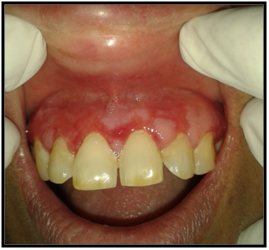

On intraoral examination, diffuse lesions in the form of erythematous areas were seen interspersed within white keratotic areas present all over the facial aspect of gingiva (Figure 2) and more posteriorly on the buccal mucosae bilaterally (Figure 3). Left buccal mucosa showed a white erythematous patch measuring approximately 2x2.5cms extending anteroposteriorly from the area adjacent to mandibular first molar to the retro molar pad area and superior inferiorly from the line of occlusion to the upper and lower lingual vestibule. White radiating striae (wickhamstriae) were present with an interspersed erythematous patch. Right buccal mucosa showed a more extensive lesion measuring approximately 2.5x3cms extending anteroposteriorly from the region adjacent to mandibular canine to the retromolar pad area and superioinferiorly from the upper gingiva buccal sulcus to the lower gingivobuccal sulcus and the alveolar mucosa. Borders of the lesion appear irregular and ill defined. On palpation, the lesions appeared to be tender. The surface of the lesions were rough and non scrapable with no induration noted.

Figure 3 The lesion on the facial gingiva.